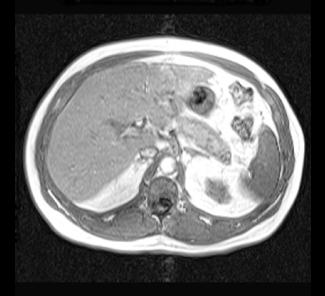

These are both MR images (note the dark appearance of bone and high signal fat). The image on the left is an in-phase image and the image on the right is an out-of-phase image, which causes a number of artifacts (a black outline around many structures, called 'India Ink' appearance) but also causes signal from fat to decrease. The liver is brighter on the in-phase than the out-of-phase image, indicating that it has diffuse fatty infiltration. MR is not used as frequently as CT overall in abdominal imaging, but can solve particular problems, such as detecting small amounts of fat within organs or lesions, which can often help in the differential diagnosis of complex cases.